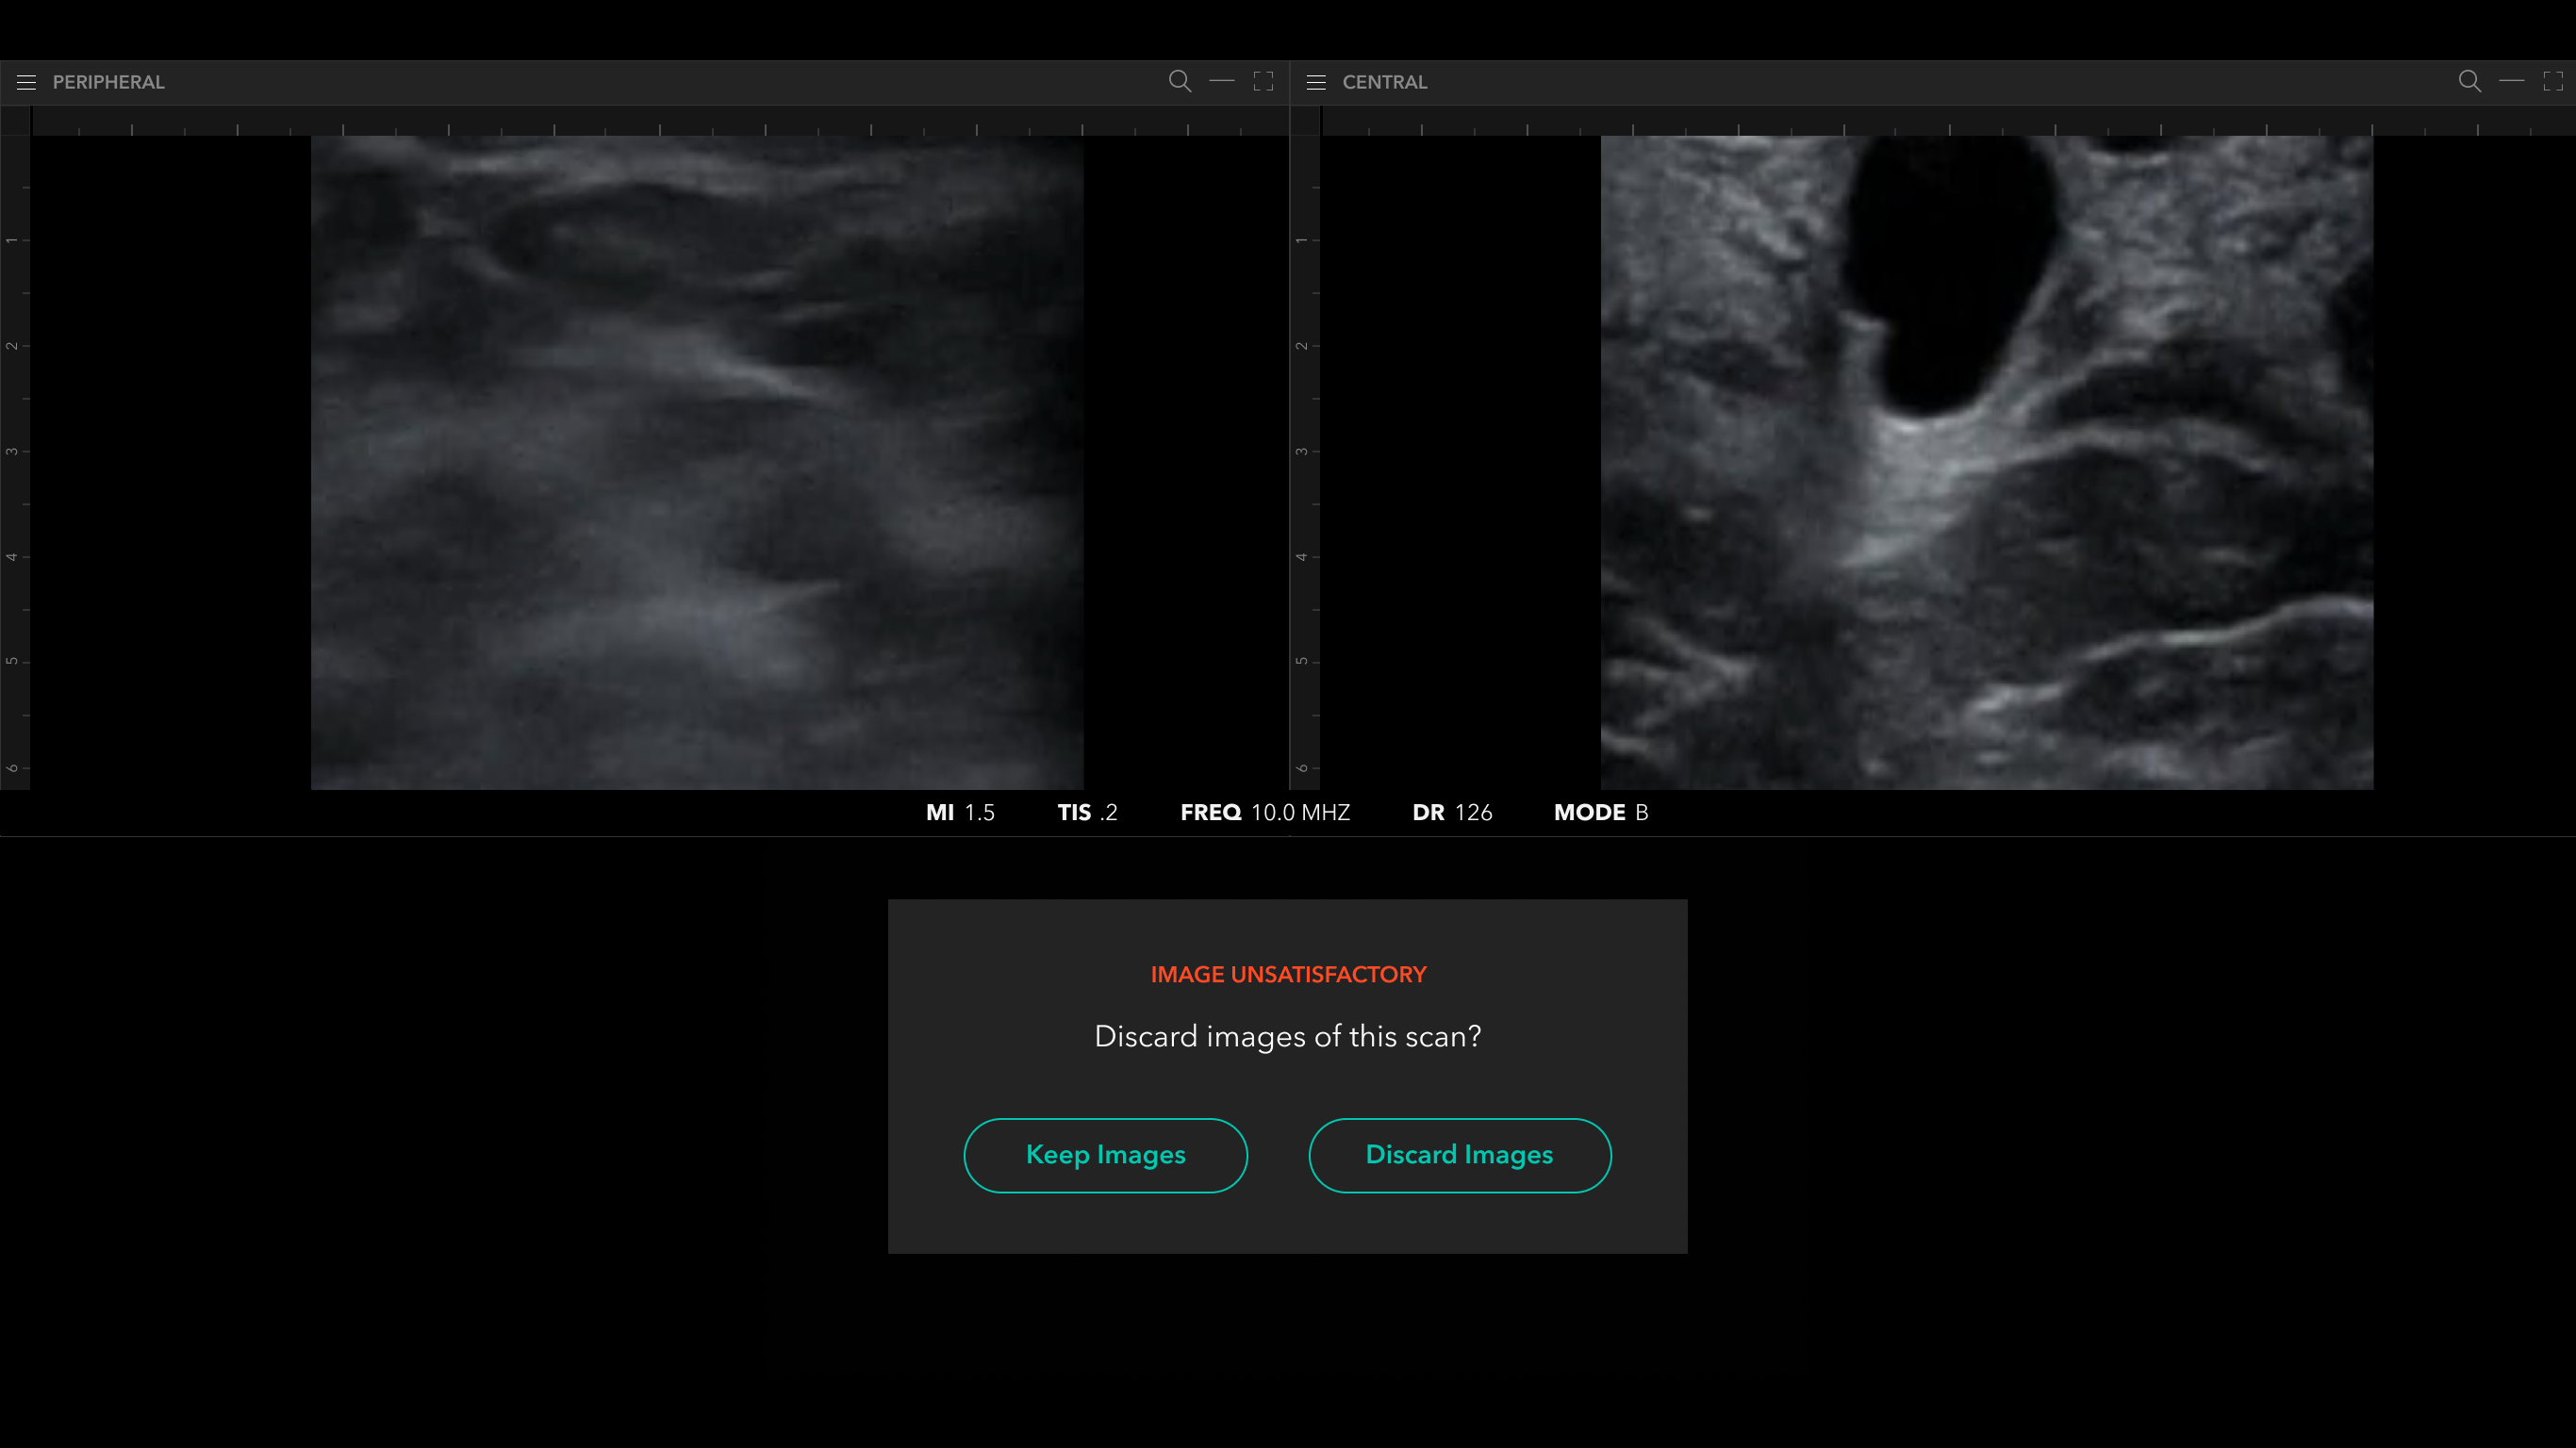

Scan Flow

Post Scan / Labeling And Annotation